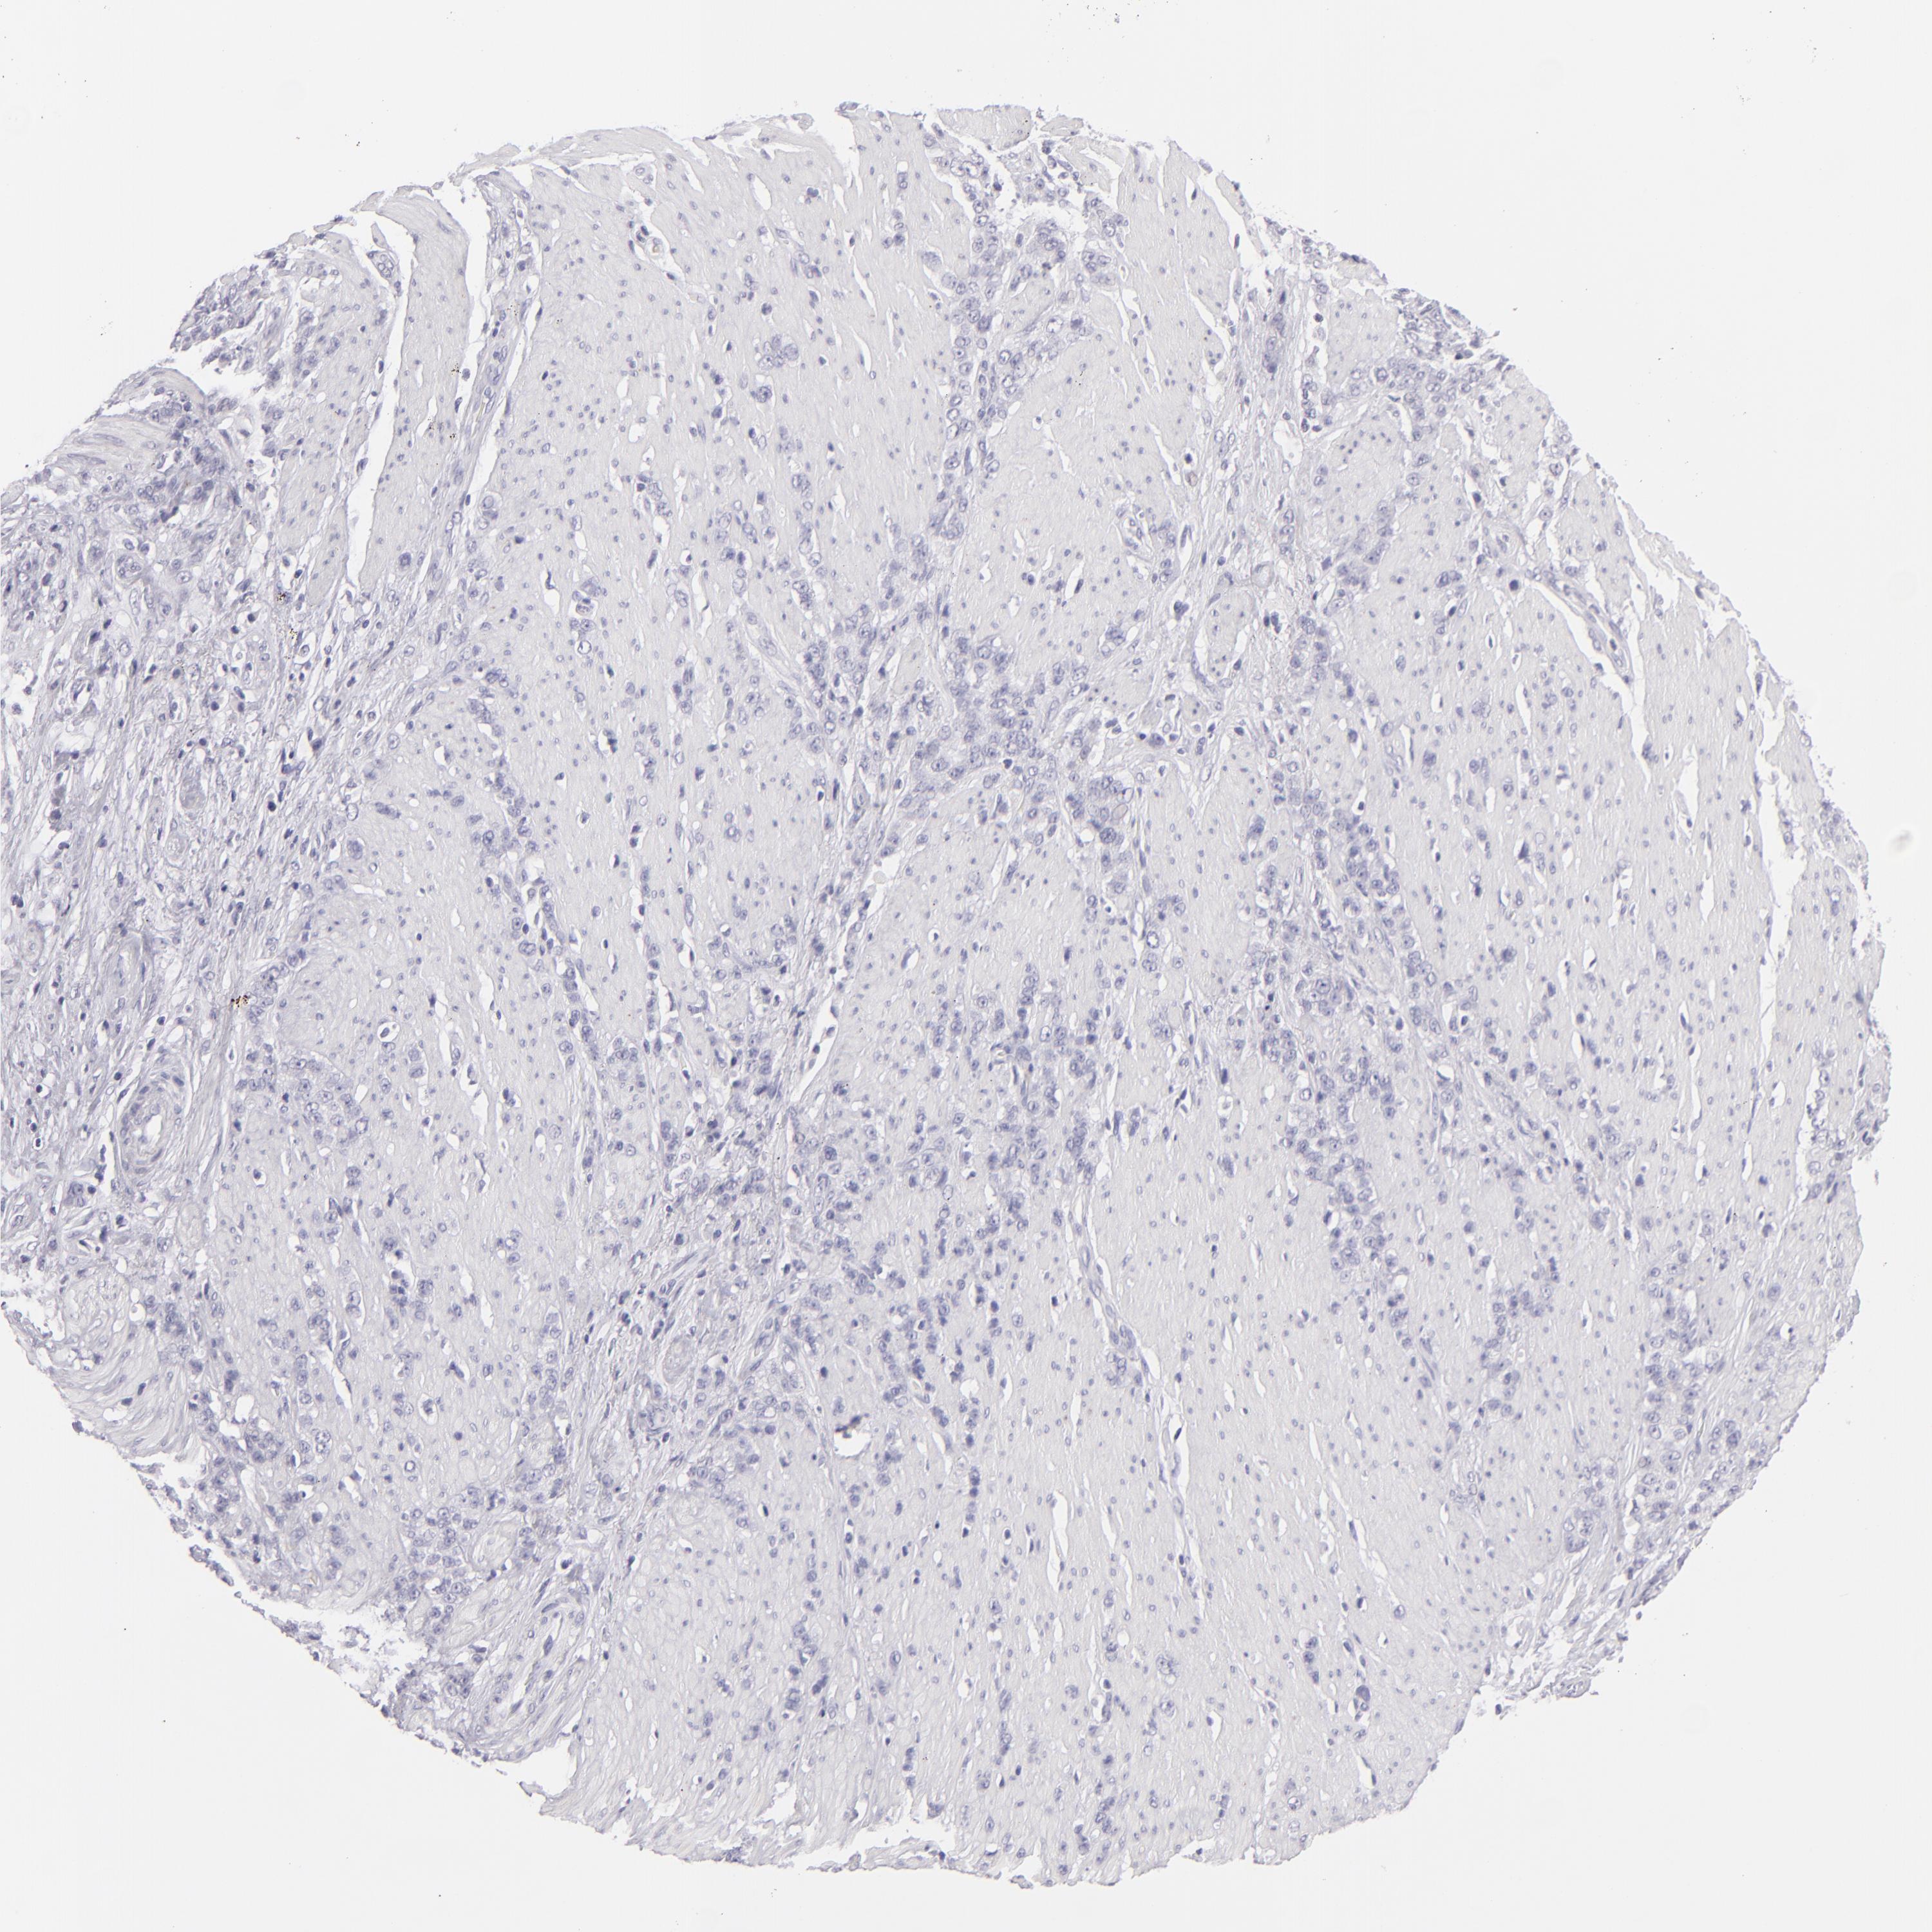

STOMACH CANCER - Protein expressioni

A mouse-over function shows sample information and annotation data. Click on an image to view it in a full screen mode. Samples can be filtered based on level of antibody staining by selecting one or several of the following categories: high, medium, low and not detected. The assay and annotation is described here.

Note that samples used for immunohistochemistry by the Human Protein Atlas do not correspond to samples in the TCGA dataset.

Antibody stainingi

Antibody staining in the annotated cell types in the current human tissue is reported as not detected, low, medium, or high, based on conventional immunohistochemistry profiling in selected tissues. This score is based on the combination of the staining intensity and fraction of stained cells.

Each image is clickable and will lead to virtual microscopy that enables deeper exploration of all samples and also displays staining intensity scores, fraction scores and subcellular localization as well as patient and tissue information for each sample.

Antibody HPA044848

Antibody HPA056897

Antibody CAB002450

Adenocarcinoma, NOS

Adenocarcinoma, High grade